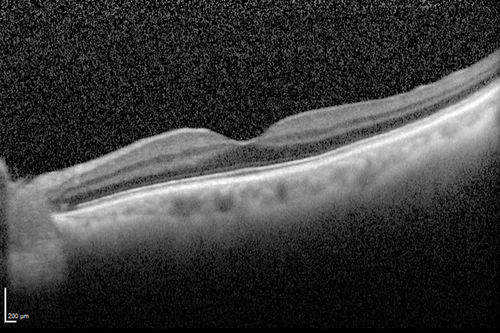

Macroaneurysm - Resolved without treatment

87 year old female with vision loss OD. Initial FA showed no leakage so no treatment was done and the fluid absorbed over 4 months. Initial VA 20/100, Final VA 20/80